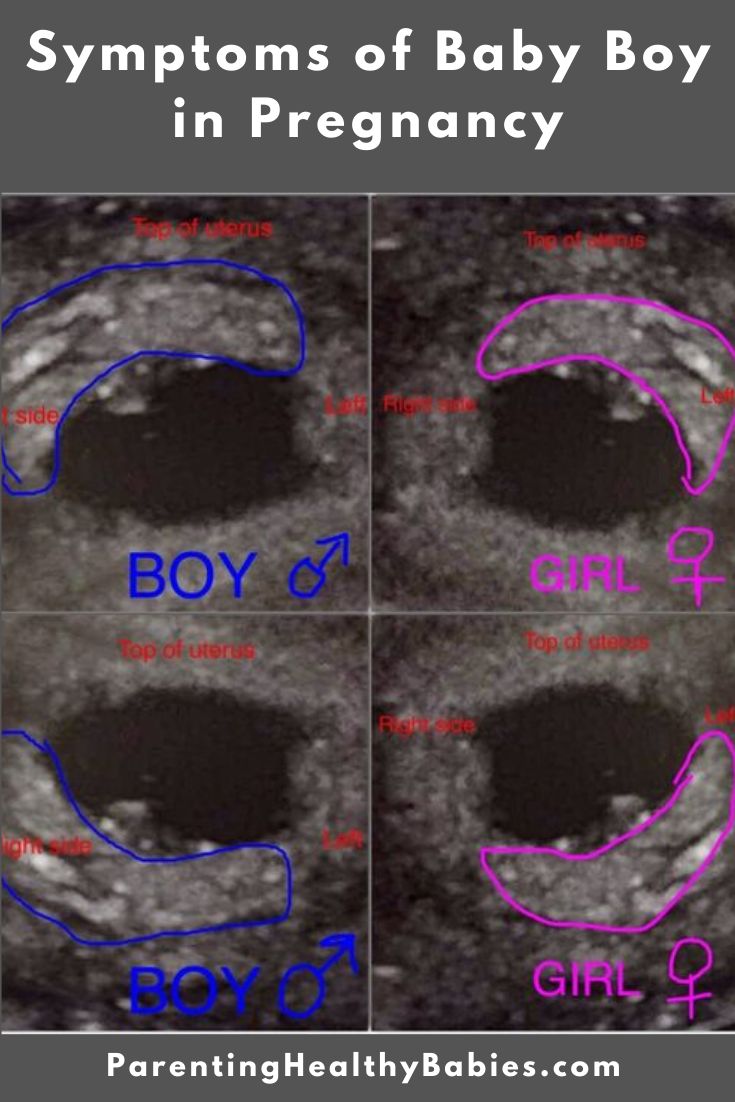

10 Weeks Pregnant Symptoms Of Boy 10 Weken Zwanger Symptomen Van Jongen: Feiten & Fabels

10 weeks pregnant symptoms of boy: Lees meer over mogelijke symptomen rond 10 weken zwangerschap als je in verwachting bent van een jongen.